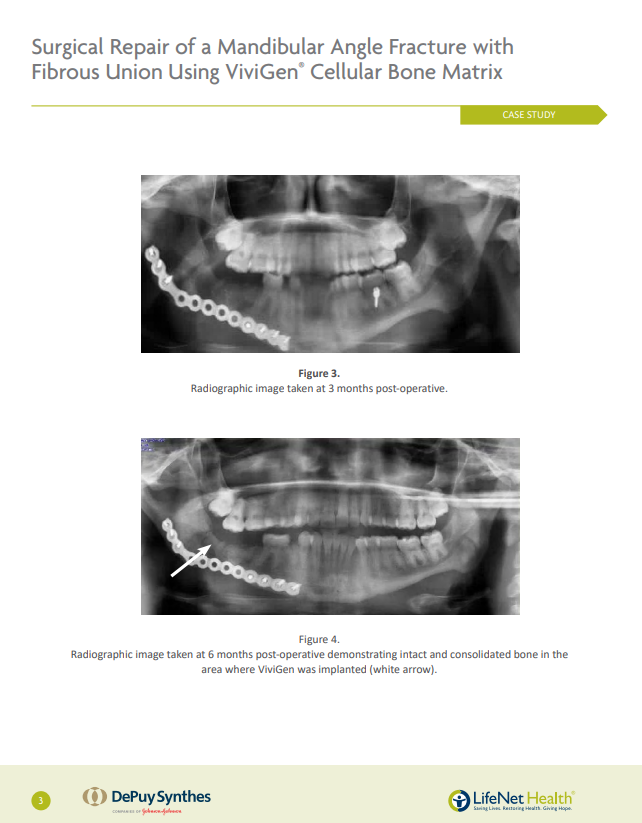

Surgical Repair of a Mandibular Angle Fracture with Fibrous Union Using ViviGen® Cellular Bone Matrix

Case performed by: Brian Smith DMD, MD; Kaushik H. Sharma, BDS, DMD; Weronika Bluma, DMD, Camden, NJ, USA